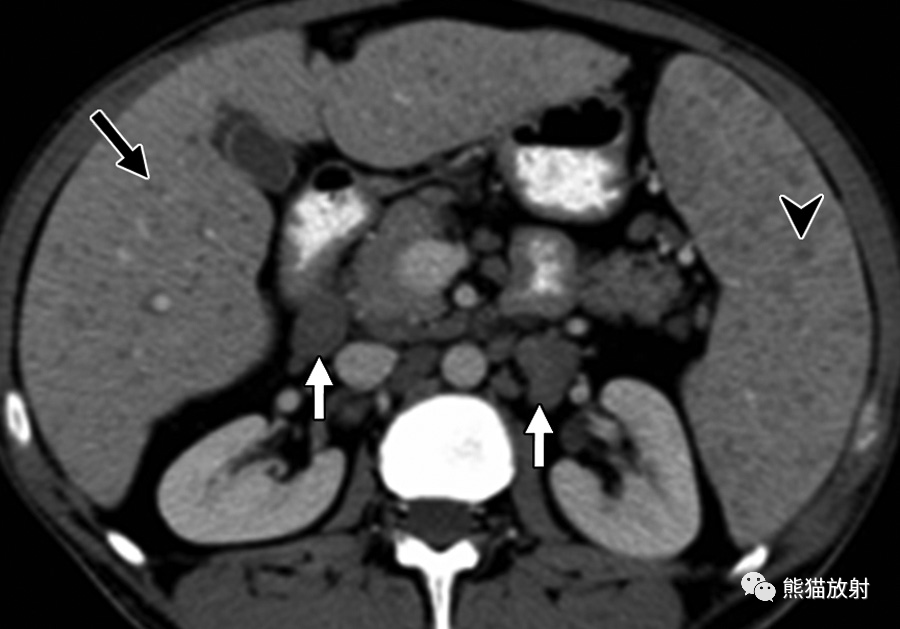

24岁男性,HIV感染患者,盗汗、发热,播散性结核感染。对比增强CT显示肝脏(黑箭)和脾(箭头)实质内多发微小低密度病变,腹膜后多发增大淋巴结(白箭)。

6岁男孩,肝巴尔通体病,被猫抓伤后发热3周。轴位增强CT图像显示多个低密度肝结节(箭)及门静脉周围增大淋巴结(箭头)。这些病变与转移瘤鉴别困难。然而,在无已知恶性肿瘤的免疫功能正常的年轻患者中观察到多发性肝脏病变应考虑到有肝巴尔通体病的可能。